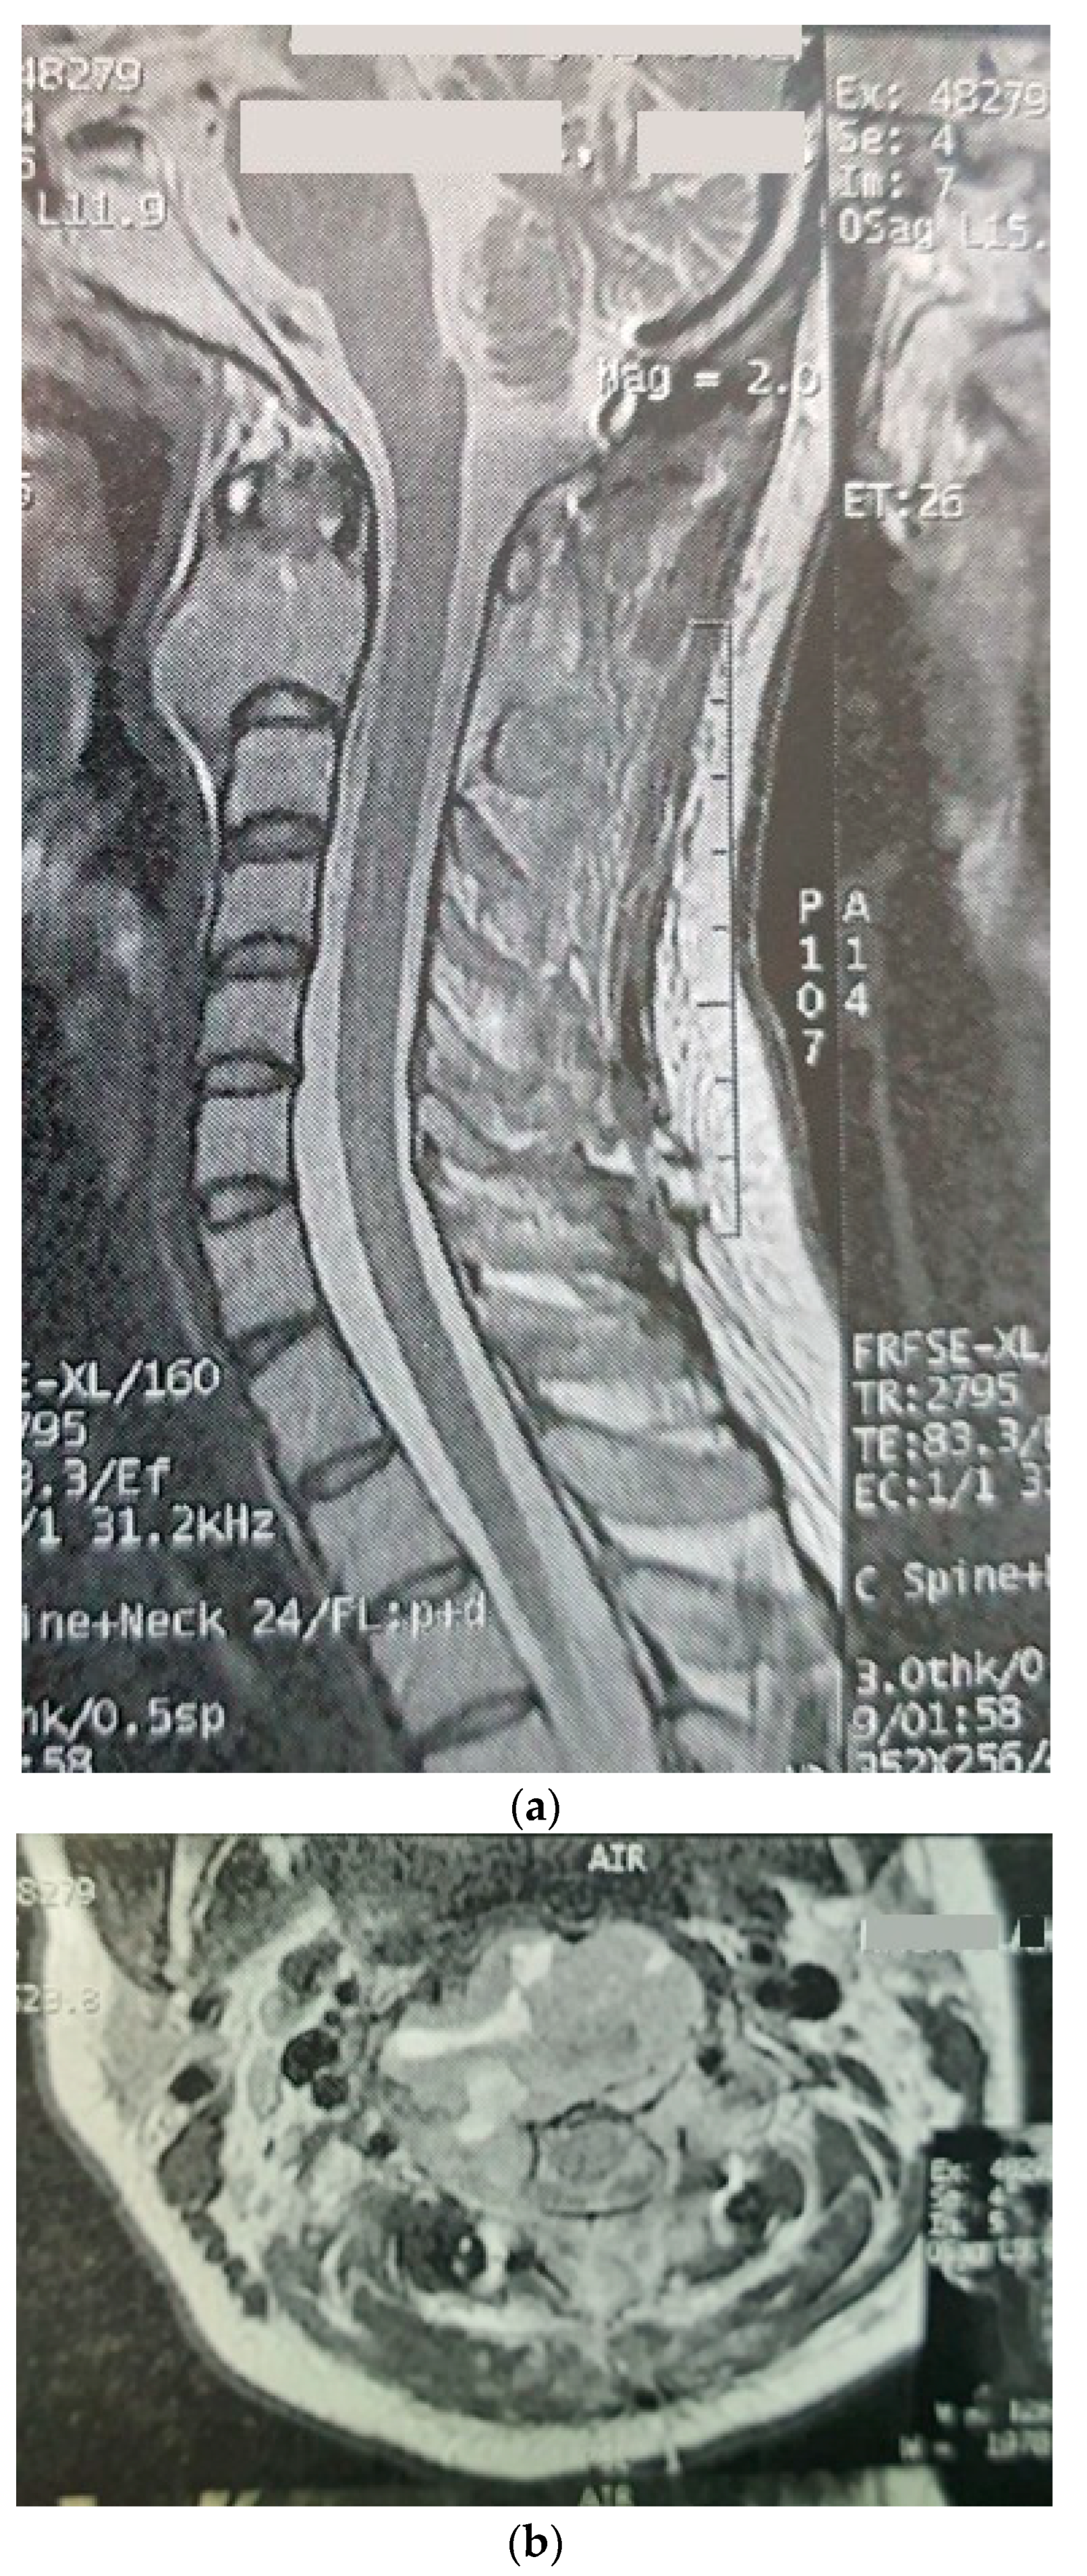

| The current case | 29, female | C2 | CD45, CD43, CD68, S100 | Surgery and radiotherapy | Brain metastasis after 9 months |